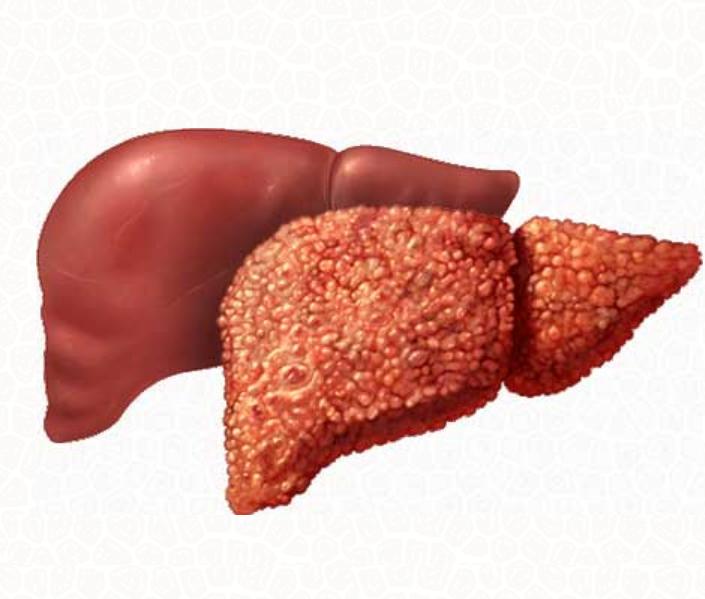

Изображения заболеваний печени: признаки и симптомы